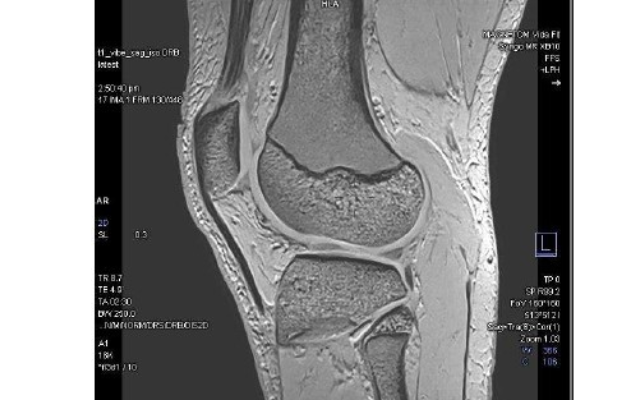

The pelvic floor is a complex area, so if the cause of symptoms isn’t clear, or if surgery is being considered, additional imaging may be helpful to understand how the pelvic floor is functioning. This involves dynamic imaging (where you’re asked to bear down or have a bowel motion) using special X-rays, ultrasound, or a MRI scan. At Canopy Imaging, we use MRI to assess pelvic floor problems, and have trained staff who specialise in this type of imaging.

Pelvic floor MRI (Magnetic Resonance Defaecating Proctography) is a specialised scan that uses magnetic fields to create images of your pelvic organs and muscles, allowing our team to see how these structures move when you're relaxing, straining, and passing a bowel motion. The scan is non-invasive, painless, and does not use radiation.

Pelvic floor MRI allows doctors to assess both the pelvic organs and the support structures (muscles and ligaments), and to identify problems such as prolapse, blocked bowel emptying (obstructed defaecation), internal folding of the bowel (intussusception), or problems coordinating the pelvic floor muscles (dyssynergia).